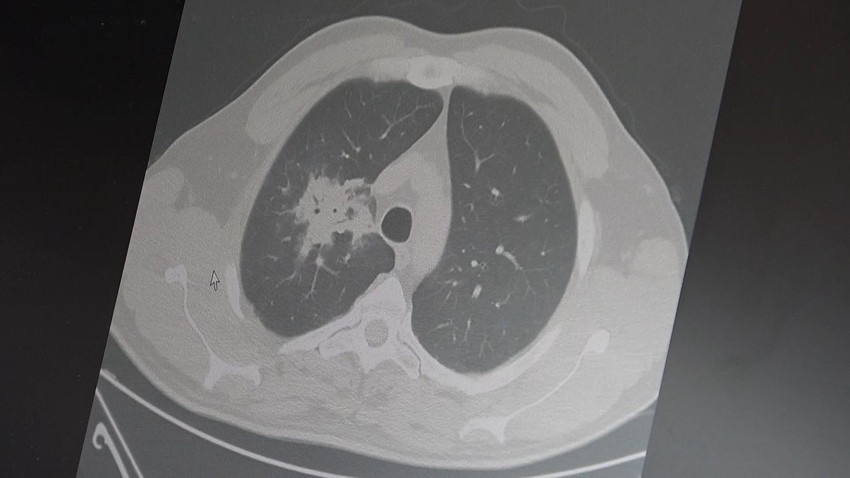

100'den fazla bilimsel çalışmanın incelendiği kapsamlı analizlere dikkat çeken Özkaya, elektronik sigaraların özellikle temas ettiği akciğer ve ağız bölgelerinde kanser riskini artırabileceğine dair güçlü bulgular bulunduğunu belirtti. Uzun vadeli sonuçların henüz tam olarak ortaya çıkmadığını ancak erken uyarı işaretlerinin ciddi olduğunu vurguladı. Araştırmalarda insan, hayvan ve laboratuvar verilerinin birlikte değerlendirildiğini aktaran Özkaya, elektronik sigaraların içerdiği kimyasalların hücre düzeyinde zarara yol açtığının ortaya konulduğunu ifade etti.

Elektronik sigaraların DNA hasarı, oksidatif stres ve kronik iltihaplanma gibi kanser gelişiminde kritik rol oynayan üç temel mekanizmayı tetiklediğini belirten Özkaya, "Bu üç faktörün doğrudan kanser oluşumuna neden olduğunu biliyoruz" şeklinde konuştu.

2024 yılında yayımlanan bir çalışmaya da değinen Özkaya, hem geleneksel sigara hem de elektronik sigara kullanan bireylerde akciğer kanseri riskinin, sadece sigara içenlere göre dört kat daha fazla olduğunun bildirildiğini kaydetti.